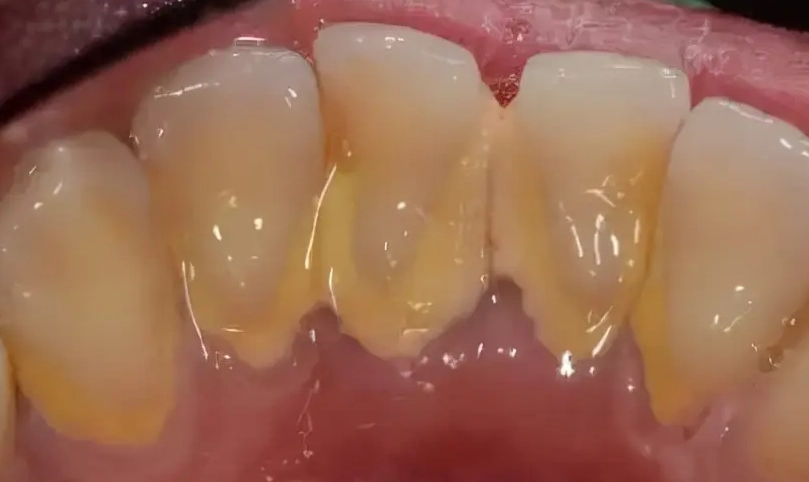

牙結石就是牙菌斑鈣化後的硬塊,通常堆積在牙齒和牙齦交界處,光靠刷牙很難清掉。洗牙機,也叫水牙線,用高壓水流沖洗這些死角。我自己發現,即使每天刷牙,牙縫後方還是會積一點黃色垢,那就是牙結石的前身。

牙結石如果不處理,會慢慢導致牙齦炎甚至牙周病。洗牙機能輔助清潔,但對於已經形成的硬塊,還是得靠牙醫的超音波洗牙。家用洗牙機更適合日常維護,防止新結石生成。